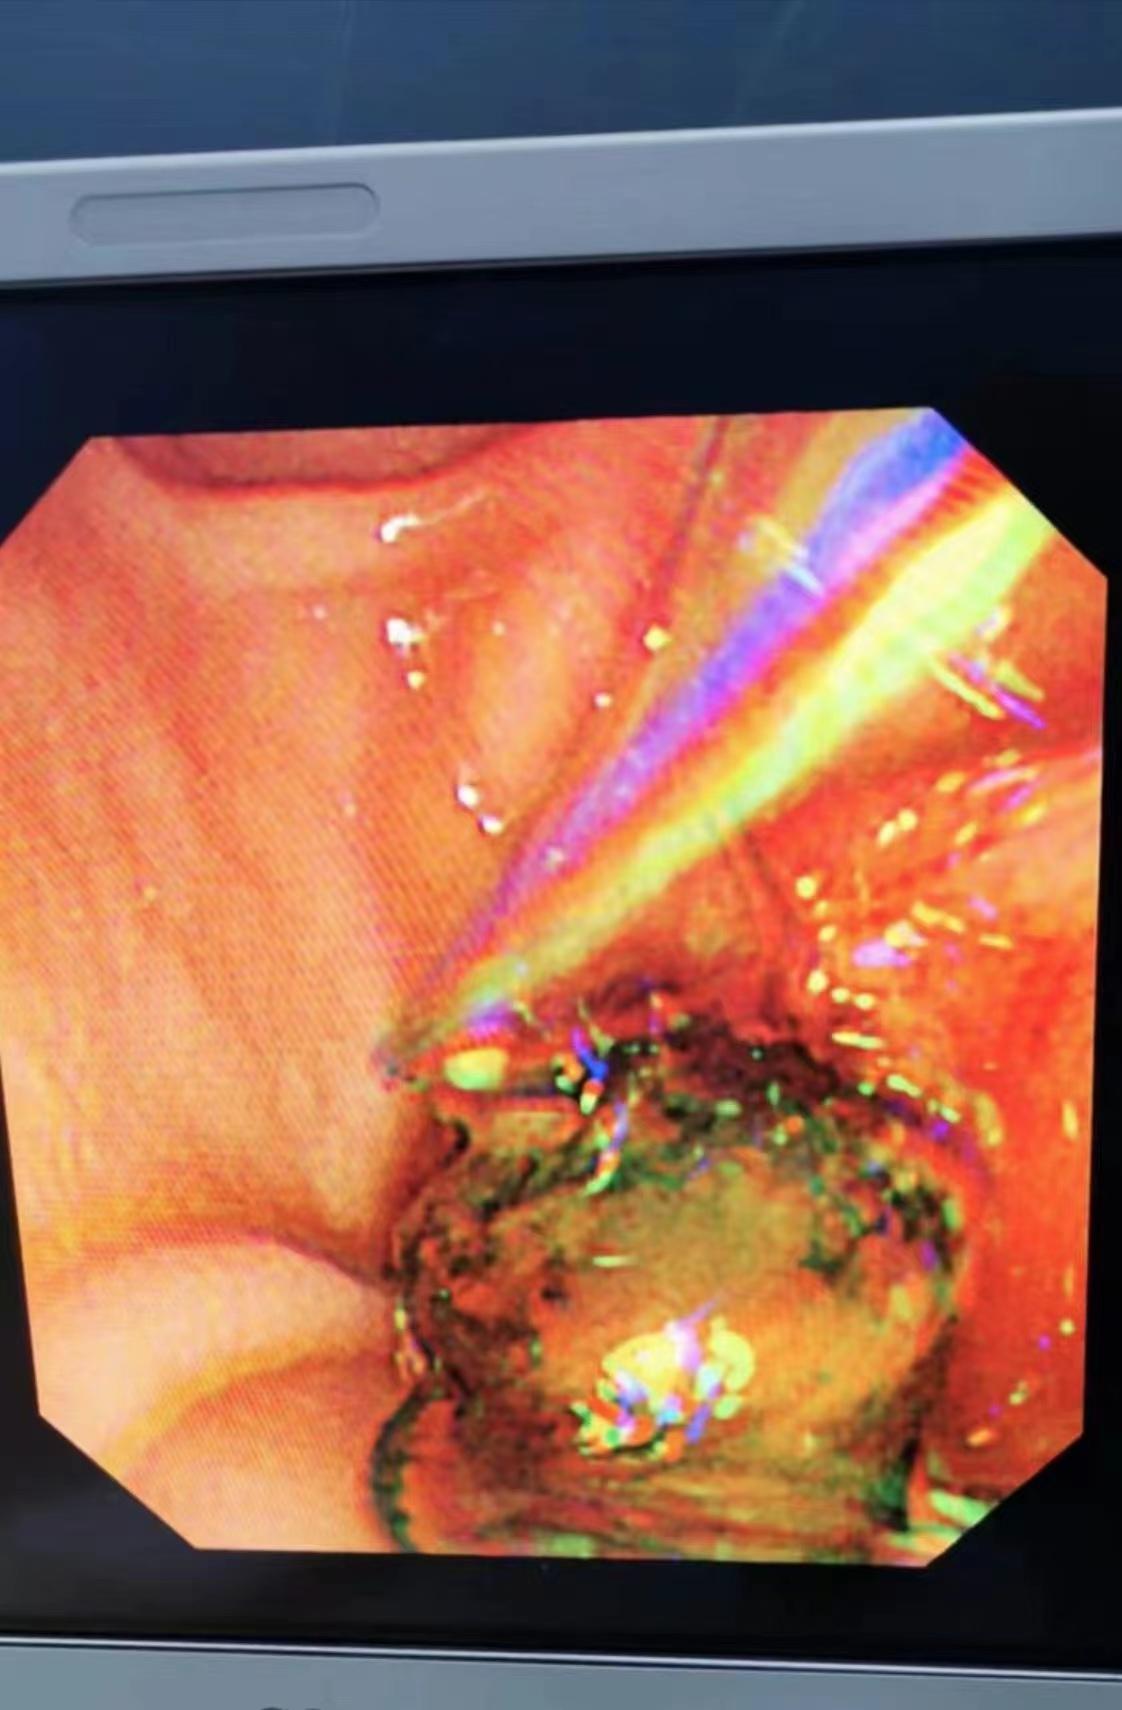

近期我院消化內(nèi)科于12月5日開展了一臺ERCP取石手術,患者楊某某,女,40歲,因“全腹脹1月,尿色深、鞏膜黃染1周”入院,12月4日查肝功能示:ALT698.4u/l,AST278.7u/l,ALP448Iu/l,γ-GT1155Iu/l,總膽紅素22.6umol/l,直接膽紅素14.3umol/l,上腹部MRI+MRCP示:膽總管低信號,考慮結石,經(jīng)全科討論后診斷、指針明確,擬行ERCP及相關技術取石治療, 術中過程通過進境,插管,造影,乳頭擴約肌切開,球囊擴張,取石球囊、取石網(wǎng)籃取出結石,最后留置鼻膽管引流,術后患者未訴特殊不適,監(jiān)測生命征平穩(wěn),術后3h、12h及24h淀粉酶正常,術后24h復查肝功能:ALT233.4u/l,AST38.5u/l,ALP266Iu/l,γ-GT713Iu/l,12-9復查肝功能:ALT103.u/l,AST28u/l,ALP184Iu/l,γ-Gt477Iu/l,患者病情明顯好轉,順利出院。